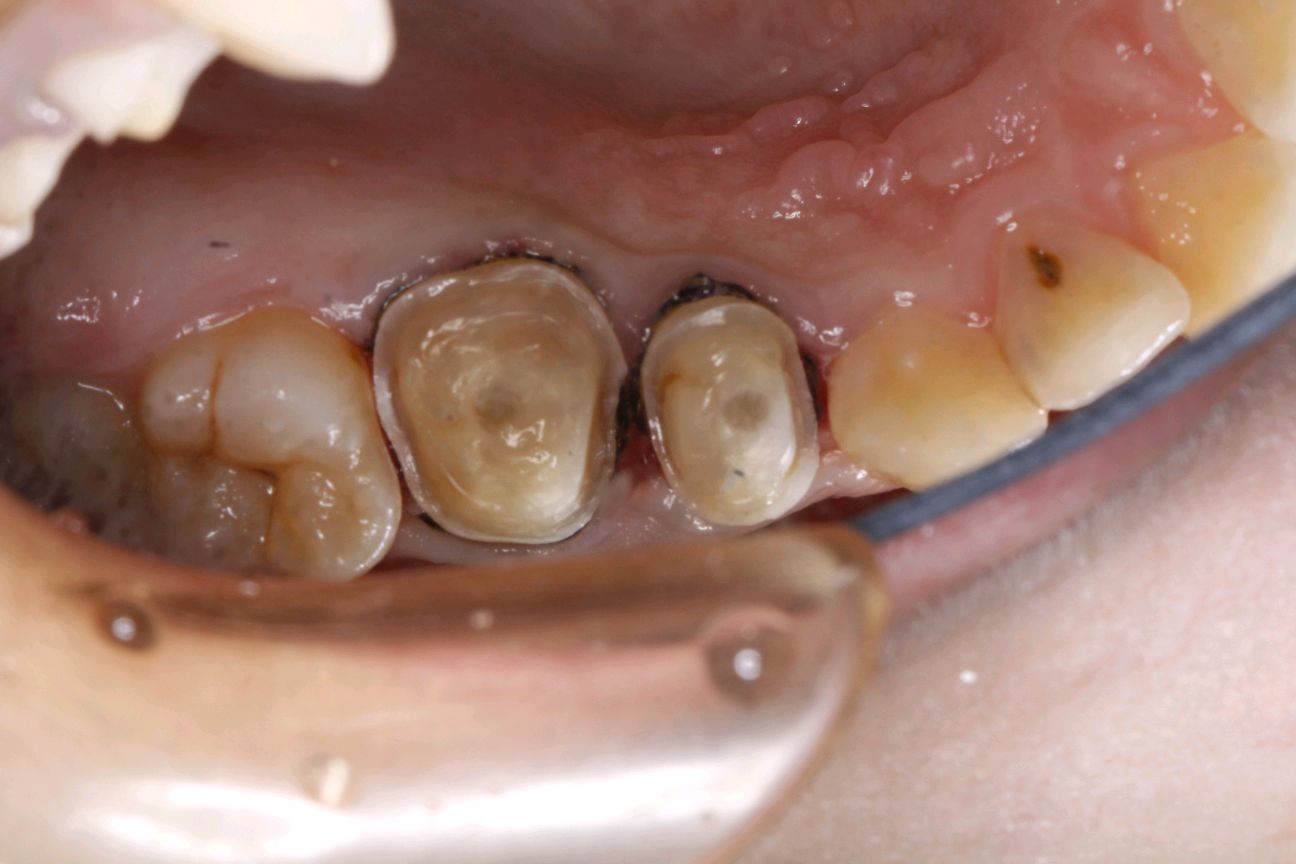

患者女,二十三岁,右上后牙食物嵌塞前来就诊。检查发现15。16,邻颌面大面积龋坏,牙体结构也发生了缺损,通过X线显示龋坏及髓,根尖大面积低密度影像。

治疗计划:根管治疗+纤维桩+高嵌体修复

术前